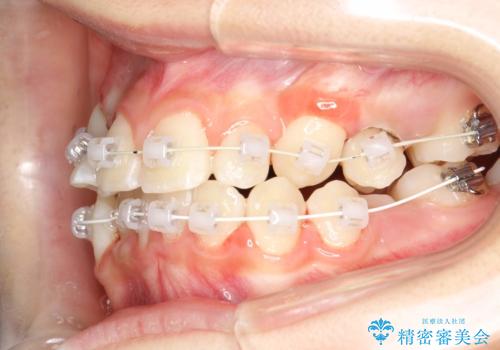

- 審美装置、リンガルアーチ

過剰歯と乳歯を抜歯後、リンガルアーチを用いて大まかな移動を行った後、マルチブラケットへ移行し、可及的に正常咬合へと誘導することを試みた。

乳歯・過剰歯を除去し、リンガルアーチを用いて埋伏していた犬歯を牽引、その他おおまかな動きを行った後、マルチブラケットにて永久歯の咬合を誘導しました。